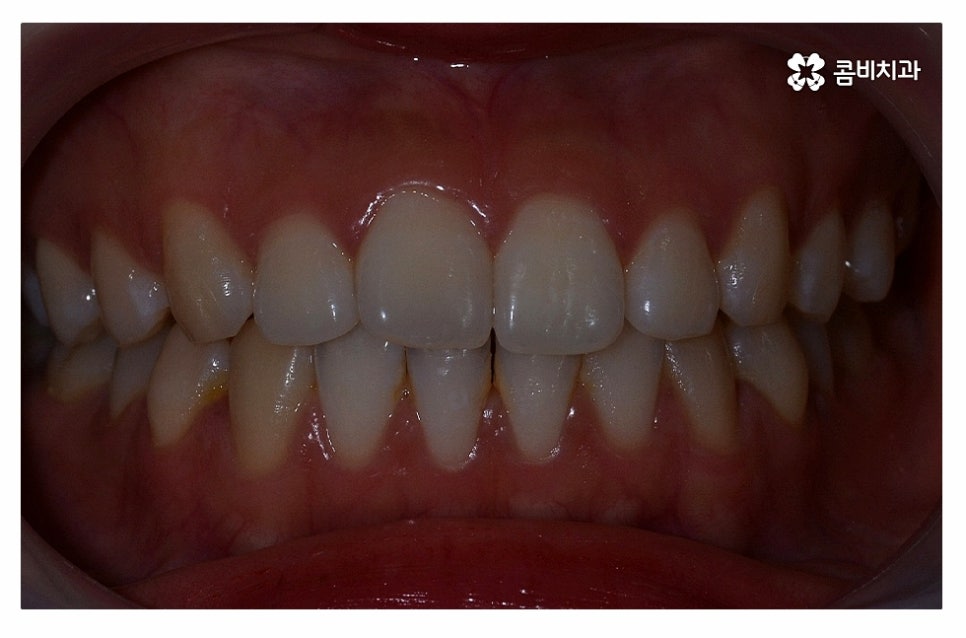

위 환자분의 경우 정면에서 보이는 치열은 가지런한 편이지만

치아가 돌출되어 돌출입으로 고민했던 사례이며

치아의 이동 공간 확보를 위해 발치 교정을 진행한 사례라고 할 수 있어요.

돌출입치아교정을 고민하는 분들 중에서는 치열이 심하게 불규칙하거나

부정교합, 안면비대칭 등으로 치료를 결심하시는 분들도 많이 있을 거예요.